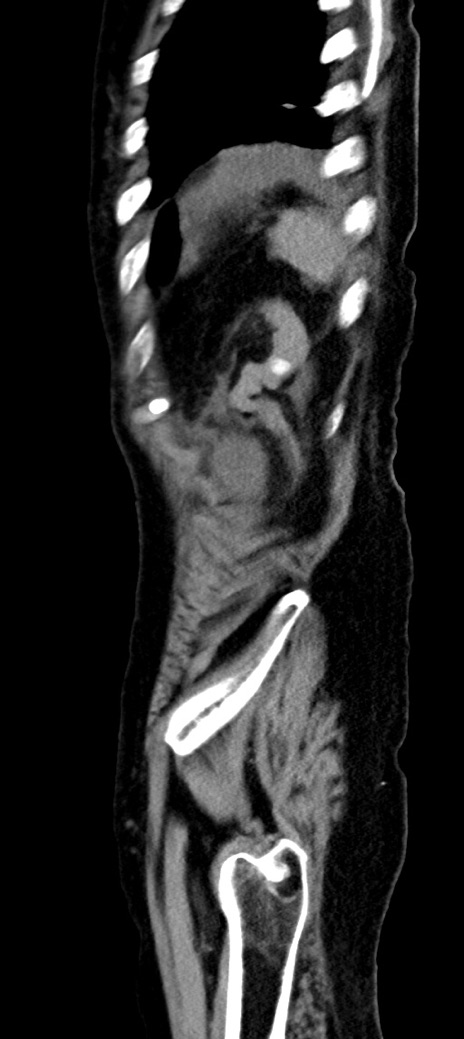

横断像

冠状断像

他院CT